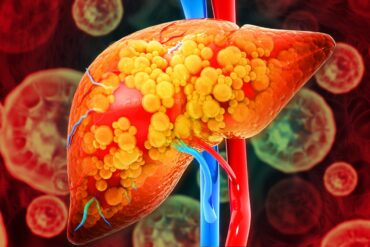

O que o fígado realmente precisa para funcionar de forma saudável

O fígado é um dos órgãos mais vitais do corpo humano e, ao mesmo tempo, um dos mais silenciosos. Ele participa de quase todas as...